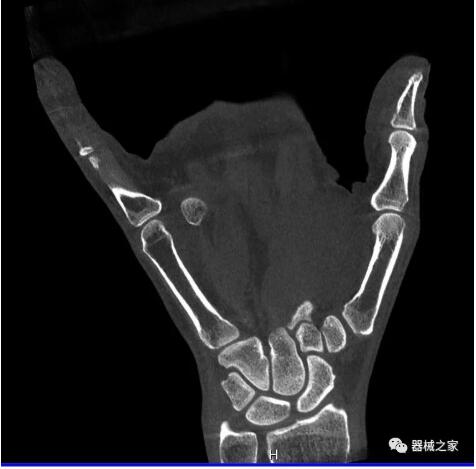

另外一款被稱為世界上最小的CT,它的重量?jī)H300磅,不僅能夠掃查足部,還可以檢查膝蓋和上肢等。

與上面介紹的CT一樣,它同樣具有輻射低、占地空間小(23*36)的特點(diǎn),隨開(kāi)隨用(支持直接接入墻上的插座)。

這款CT使用非常方便,通過(guò)上下移動(dòng)保持與患者的手臂或者雙腿齊平,掃描快速,僅需要30秒左右就可以完成掃查。

以上介紹的CT均來(lái)自國(guó)外同一家公司,這些CT均配置了可視化軟件,可以進(jìn)行切片、3D重建以及大型CT附帶的所有典型的操作功能。

以下是這些“特立獨(dú)行”的CT所拍出來(lái)的圖像: